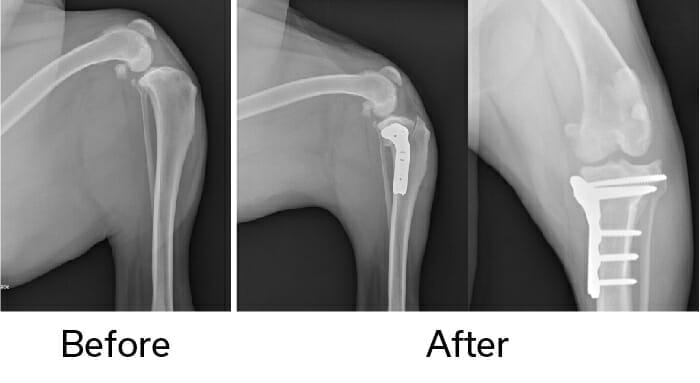

Back to the wagon analogy for the best explanation. If we take the wagon and place it on a flat road, we don’t need a rope to hold it stable. With the TPLO, the surgeon cuts the back part of the tibia with a special circular saw and rotates the piece of bone so the top of the tibia is almost flat. Then the surgeon repairs the bone with a special bone plate to hold it in place while it heals. Once the bone is healed in the “flat road” position, the tibia no longer thrusts forward when the dog walks and the knee is stabilized. The plate usually remains on the bone indefinitely, but it is no longer needed for support once the bone heals.